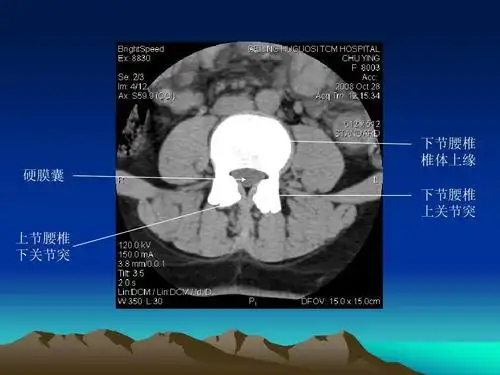

脊柱ct,mr断层解剖2

腰椎ct读片

腰椎ct诊断

腰椎ct诊断ppt